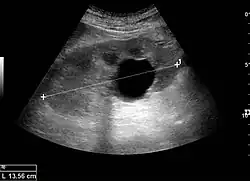

The length of the adult kidney is normally 10–12 cm, and the right kidney is often slightly longer than the left kidney. The adult kidney size is variable due to the correlation with body height and age; however, normograms for pediatric kidney size are available.[1]

Cortical thickness should be estimated from the base of the pyramid and is generally 7–10 mm. If the pyramids are difficult to differentiate, the parenchymal thickness can be measured instead and should be 15–20 mm (Figure 3). The echogenicity of the cortex decreases with age and is less echogenic than or equal to the liver and spleen at the same depth in individuals older than six months. In neonates and children up to six months of age, the cortex is more echogenic than the liver and spleen when compared at the same depth.[1]